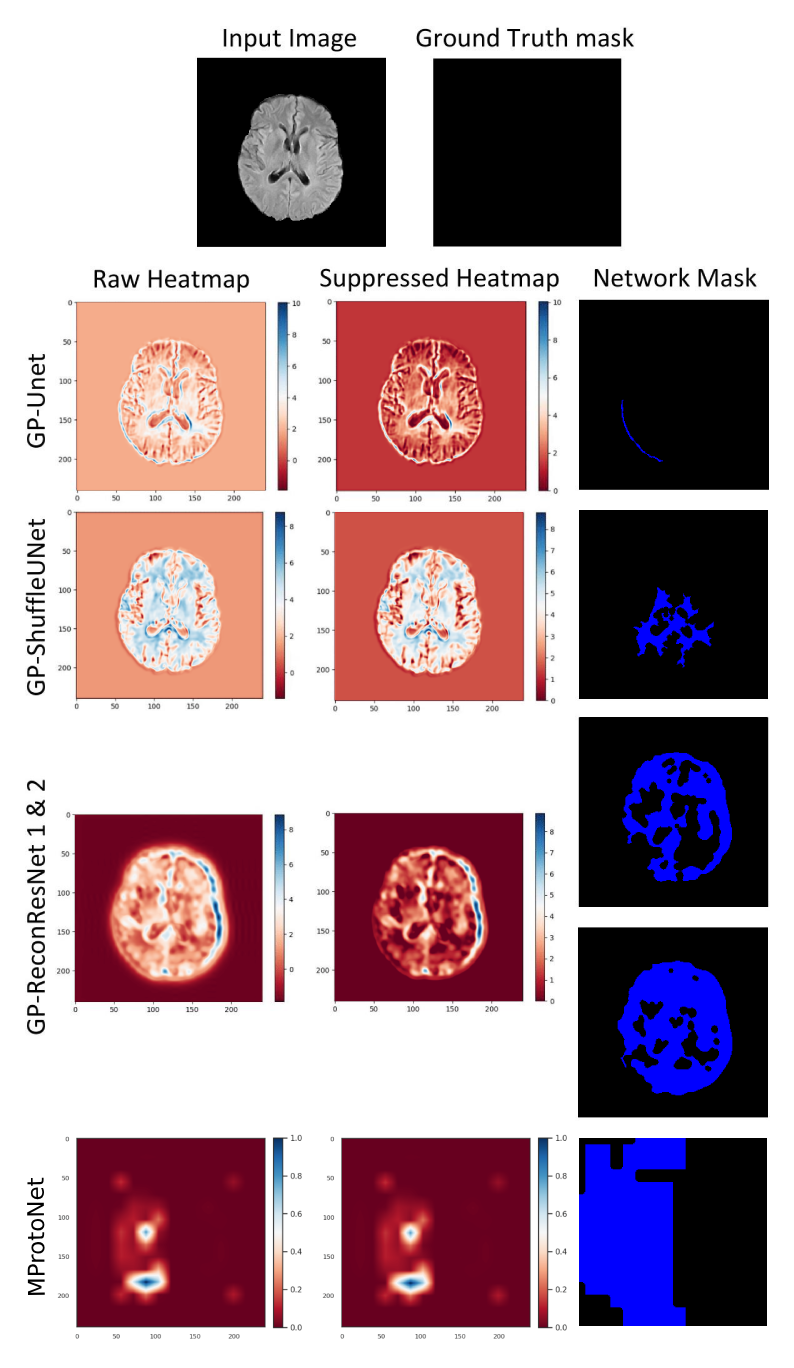

Refer to caption

Figure 10: Example results of the interpretable models’ (GP-models and baseline MProtoNet) correctly classified LGG tumour (class 1) from the BraTS 2020 dataset. 1st row is the input slice, the ground truth mask is used for comparison, and the rest of the rows are the models’ outputs. For the rest of the rows: 1st column contains the models’ predictions known as the raw heatmaps, where the red areas influenced the classification outcome negatively, and the blue areas influenced the classification outcome favourably; 2nd column contains the suppressed heatmaps, where negative values are suppressed to obtain positive attributions only; 3rd column contains the networks’ generated final masks = the suppressed heatmap + thresholding.

Figure 11: Example results of the interpretable models’ (GP-models and baseline MProtoNet) correctly classified HGG tumour (class 2) from the BraTS 2020 dataset. 1st row is the input slice, the ground truth mask is used for comparison, and the rest of the rows are the models’ outputs. For the rest of the rows: 1st column contains the models’ predictions known as the raw heatmaps, where the red areas influenced the classification outcome negatively, and the blue areas influenced the classification outcome favourably; 2nd column contains the suppressed heatmaps, where negative values are suppressed to obtain positive attributions only; 3rd column contains the networks’ generated final masks = the suppressed heatmap + thresholding.